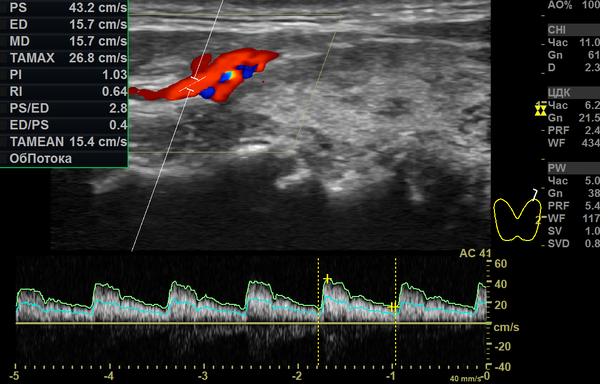

Небольшое увеличение пиковой скорости кровотока в щитовидной артерии (43,2 см/с при норме 20–30 см/с) подтверждает наличие лёгкой избыточной стимуляции железы.

Измерение скорости кровотока в артериях железы — обязательный элемент современного ультразвукового исследования.

Заключение: Ультразвуковые признаки тотального диффузного процесса в щитовидной железе с увеличением правой доли (зоб 1-й степени), с умеренными явлениями разрушительных изменений в дольках и сегментах, сопровождающихся незначительной инфильтрацией лимфоцитами. Напряжённость ткани железы (по показателям кровотока) незначительно повышена с обеих сторон. Объём относительно полноценной гормонообразующей ткани составляет около 80–85%.